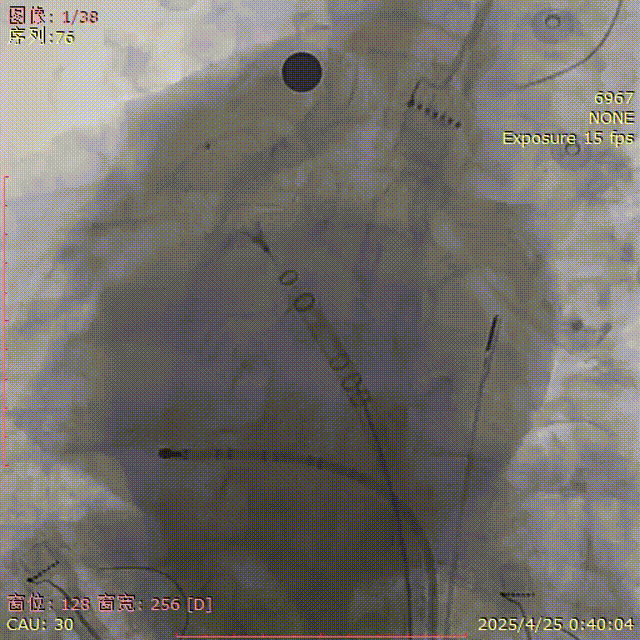

行左心耳造影,测量心耳大小,选择合适的封堵器

肝位造影

LAO 30° CAU 20°

肝位开口:25mm;深度: 24mm

选伞:FLX 31mm

展开后造影

封堵器呈热狗型,下缘轻微露肩

肝位及纯足位下缘轻微露肩(少于封堵器尺寸1/3),肩位下无明显露肩,评估符合PASS原则